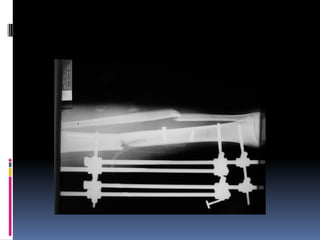

 Tại SaoTôi Phải Cố Định Xương Gãy? Bằng Cách Nào?

 Tại SaoTôi Phải Cố Định Xương Gãy? Bằng

Cách Nào?

 Tại SaoTôiPhải Cố Định Xương Gãy? Bằng Cách Nào?